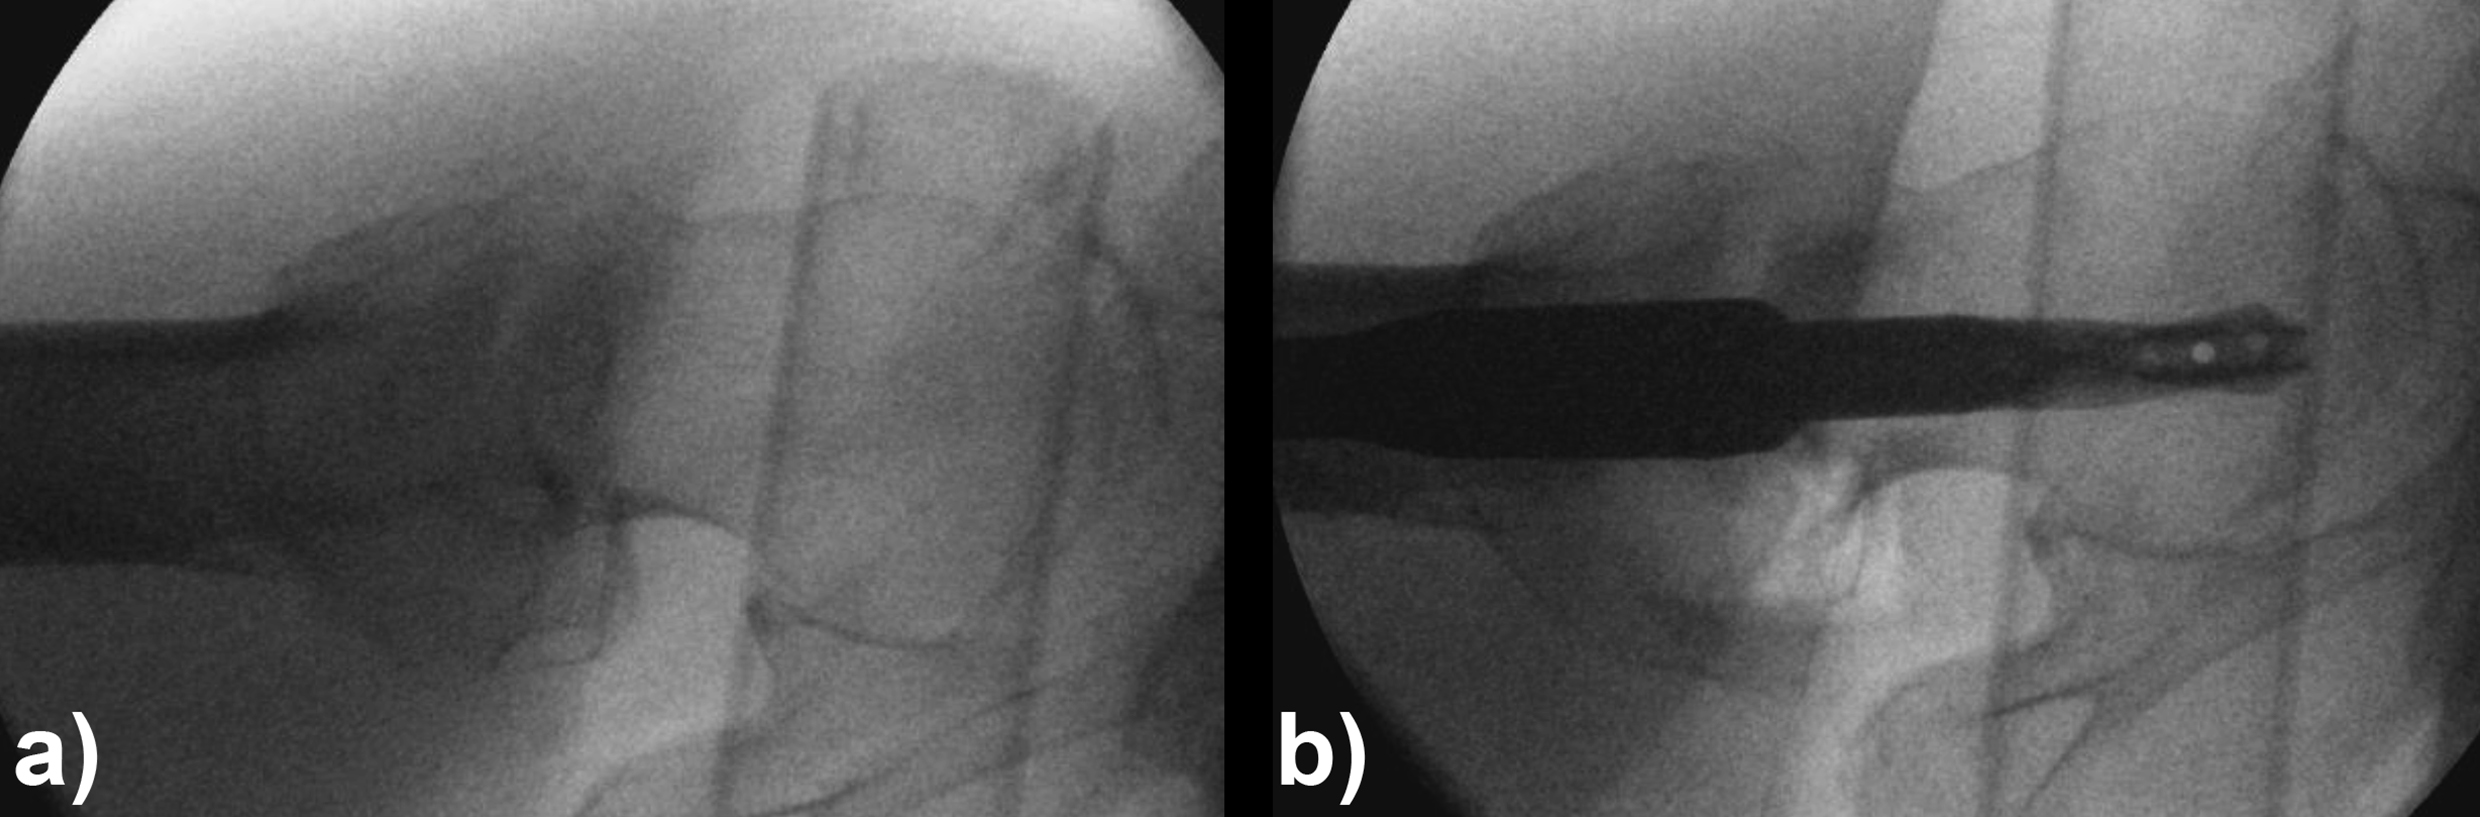

An 83-year-old female patient sustained a 31-A.2.2 fracture of the right proximal femur after a fall at home (Figs 1-2). Intraoperative and postoperative images are shown (Figs 3-5).